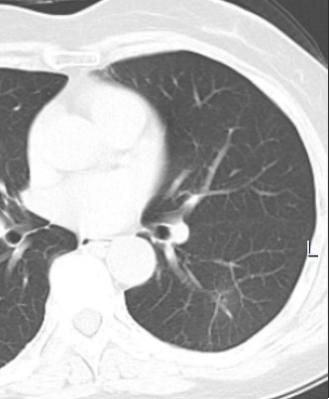

2023年6月16日,对于65岁的林女士及家人来说是个无比灰暗的日子,体检CT结果显示林女士左下肺背段有一约29×16mm(核桃大小)结节影,边缘模糊,有长毛刺,考虑肺部恶性病变,医生建议尽快进行手术治疗,这对于林女士一家人来说无异于晴天霹雳。

2016年6月16日(体检发现左下肺结节)